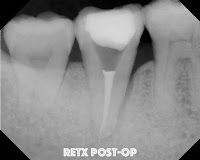

Unfortunately, at the 2 year re-evaluation, the lateral lesion did not resolve. Since I'm working on a periodontist friend of mine, why not try a retreat again?  We tried it and again found no root fracture, or obvious reason for the failure to heal.

Four years later at another re-evaluation, the bone loss on the lateral is even worse. We are still puzzled at why this has not resolved, but not convinced there is a root fracture, so we decided to try intentional replantation.   So, here are some of the best photos I have to document the process.